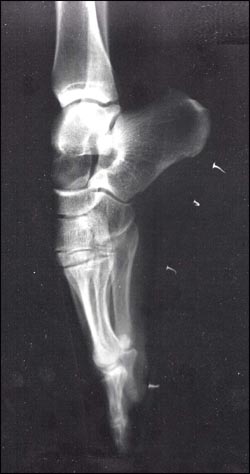

To understand the anatomy of a pointe shoe, it is first necessary to understand the anatomy of the foot. The foot is in control of the shoe, shaping it by articulating the joints throughout the foot.

The foot connects to the leg at the ankle with a saddle joint that allows for a great amount of mobility and rotation. This enables the foot to be pointed, creating a straight line through the leg and out the end of the foot. This is the desired aesthetic and creates an illusion of length. However, feet do not point from ankle mobility alone. They also depend on dexterity in the toes and flexibility in the arch. In his article, “Culture on the Ground: The World Perceived Through the Feet,” Tim Ingold (2004) states that modern humans have lost the use of dexterity in their feet, due to having them so often encased in shoes. It can be argued, however, that dancers have heightened dexterity, with their feet made all the stronger through repeated exercises performed while wearing reinforced shoes (Stern, 1980).